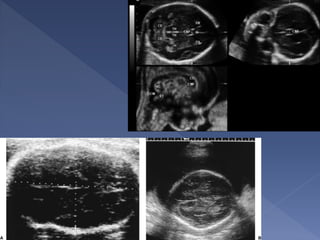

 Bi-parietal diameter

 Occipto-frontal diameter

 Head circumference

 Abdominal circumference

 Femur length

 All can be + or – 2 weeks

Landmarks :

 Midline Falx

cerebri

 Cavum septum

pellucidum

 Thalami

symmetrically

positioned on

either side of the

falx

 Lateral ventricle

 The diameter between the 2 sides of the

head

 This is measured after 13 weeks.

 Dating using the BPD should be done as

early as is feasible.

 Different babies of the same weight can

have different head size, therefore dating in

the later part of pregnancy is generally

considered unreliable

 The BPD remains the standard against

which other parameters of gestational age

assessment are compared

 A wrong measurement plane can produce

errors up to 20mm !